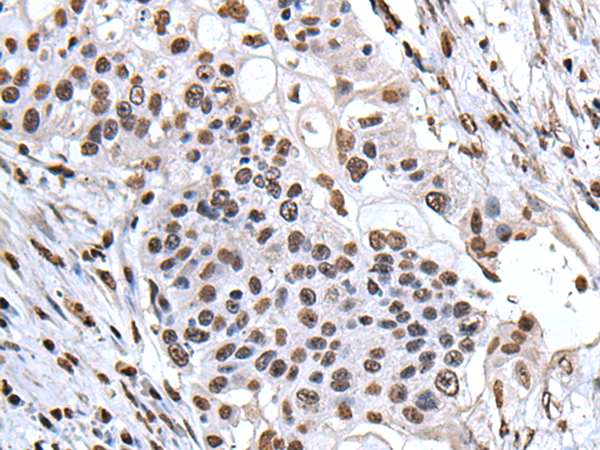

分类: 科研抗体货号: P01639别名: LANP; MAPM; PP32; HPPCn; PHAP1; PHAPI; I1PP2A; C15orf1应用: WB,IHC反应种属: Human